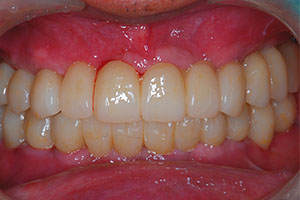

치료증례 전후사진

Before & After